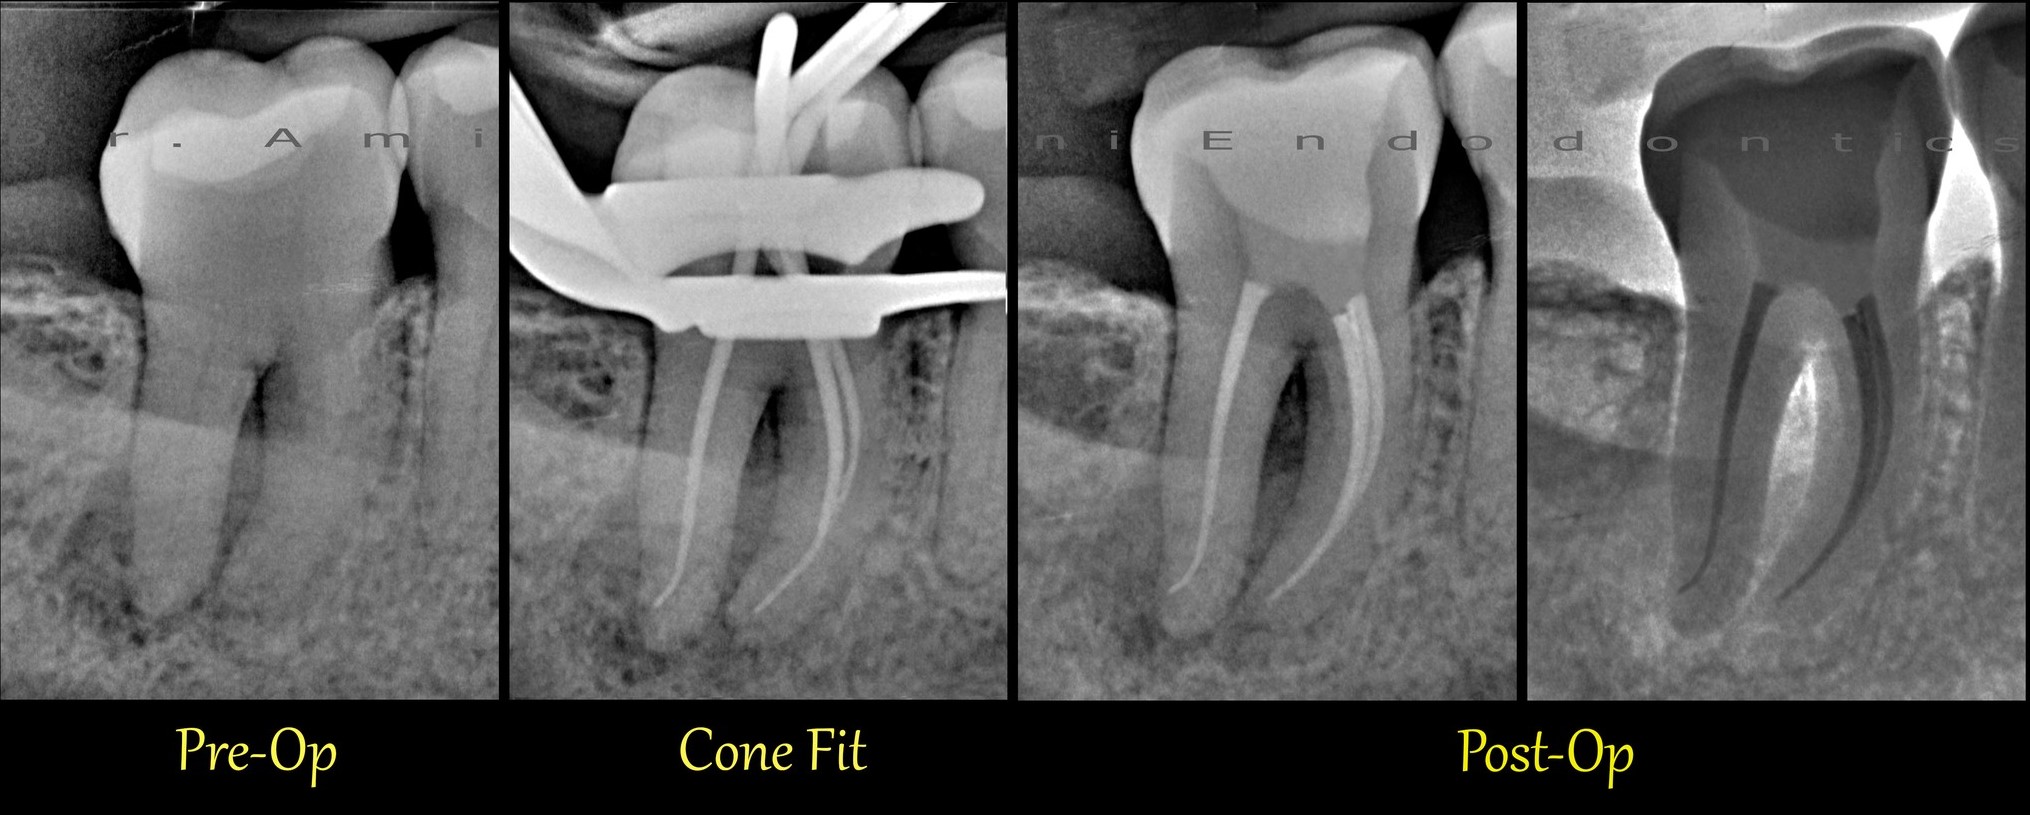

Gekrümmter Kanal im oberen Molaren